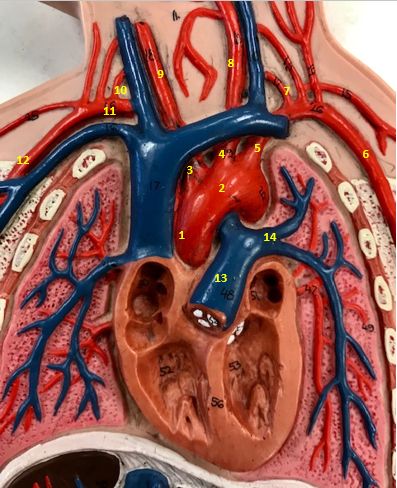

Aorta

Name #2

Brings blood out of left ventricle

Function of aorta

Brachiocephalic artery

Name #3

Supplies oxygenated blood to right arm shoulder neck and head

Function of brachiocephalic artery

Left common carotid artery

Name #4

Supplies oxygenated blood to left neck and head

Function of left common carotid artery

Left subclavian artery

Name #5

Supplies oxygenated blood to left arm shoulder

Function of left subclavian artery

Left axillery artery

Name #6

supplies blood to left armpit and upper limb

Function left axillary artery (6)

Left vertebral artery

Name #7

Supplies blood to brain and spinal cord

Function of left vertebral artery (7)

Left common carotid artery

Name #8

Supplies blood to left neck and head

Function of left common carotid artery (8)

Right common carotid artery

Name #9

Supplies oxygenated blood to right neck and head

Function of right common carotid artery (9)

Right vertebral artery

Name #10

Supplies blood to brain and spinal cord

Function of right vertebral artery (10)

Right subclavian artery

Name #11

Supplies blood to right arm and shoulder

Function of right subclavian artery

Right axillery artery

Name #12

Supplies blood to right armpit and upper limb

Function of right axillery artery (12)

Pulmonary trunk

Name #13

Bring blood out of right ventricle to lungs

Function of pulmonary trunk (13)

Left pulmonary artery

Name #14

Bring blood to left lung

Function of left pulmonary artery (14)